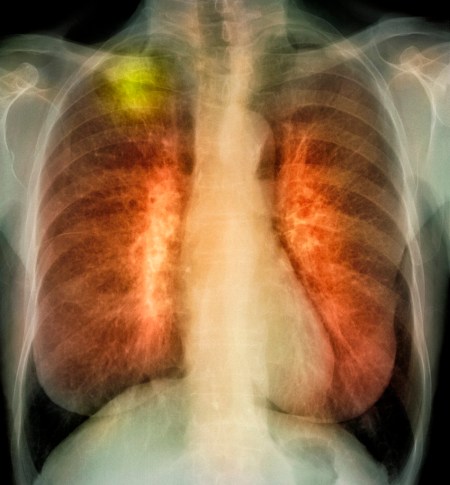

Hay que remarcar que aunque los habanos cubanos sean tan buenos, fumar es muy muy malo para nosotros. El cáncer de pulmón es la cuarta causa de muerte en Cuba.

Una Fase II de Ensayos en 2008 demostró que los pacientes de cáncer de pulmón que recibían la vacuna vivían una media de 4 a 6 meses más que aquellos que no la recibían. Este hecho provocó que Japón y algunos países Europeos iniciasen ensayos clínicos con el Cimavax también.

Para ser honestos, Cimavax probablemente no cambiará las reglas del juego en los fármacos contra el cáncer. La vacuna no ataca al tumor directamente, va contra una proteína que los tumores producen y que circula por la sangre. Esta acción hace que nuestro cuerpo libere anticuerpos contra una hormona llamada: factor de crecimiento epidermal, que normalmente causa el crecimiento de las células, y que sin control causa el cáncer.